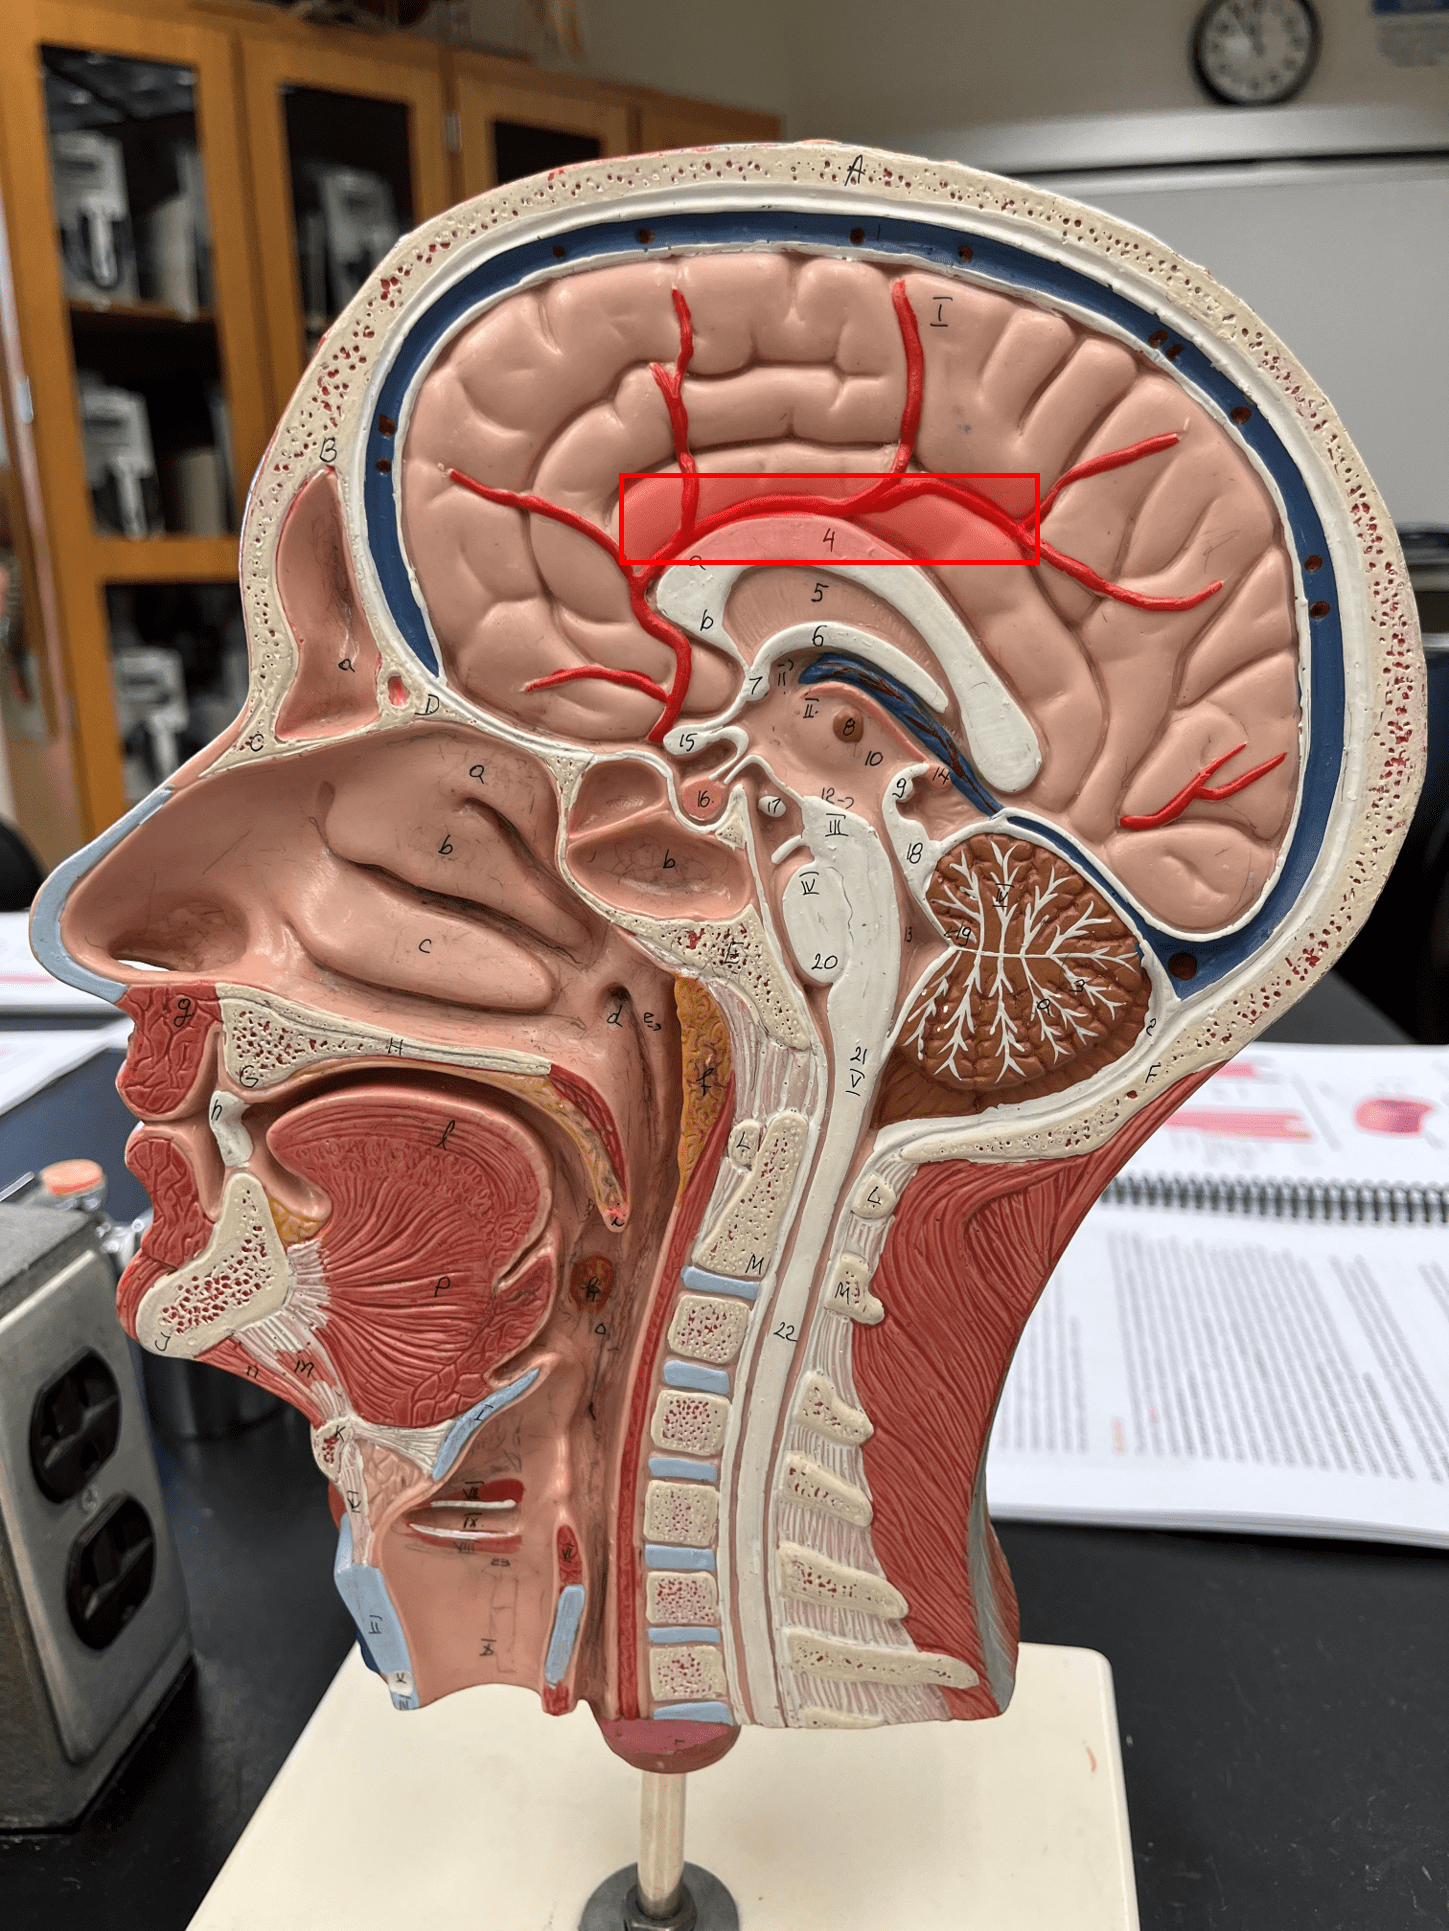

superior sagittal sinus

• A vein of the cerebral circulation.

• Drains the superficial brain.

• Empties into the internal jugular vein.

• Drains the superficial brain.

• Empties into the internal jugular vein.

34

New cards

inferior sagittal sinus

• A vein of the cerebral circulation.

• Drains the deep brain.

• Empties into the internal jugular vein.

• Drains the deep brain.

• Empties into the internal jugular vein.